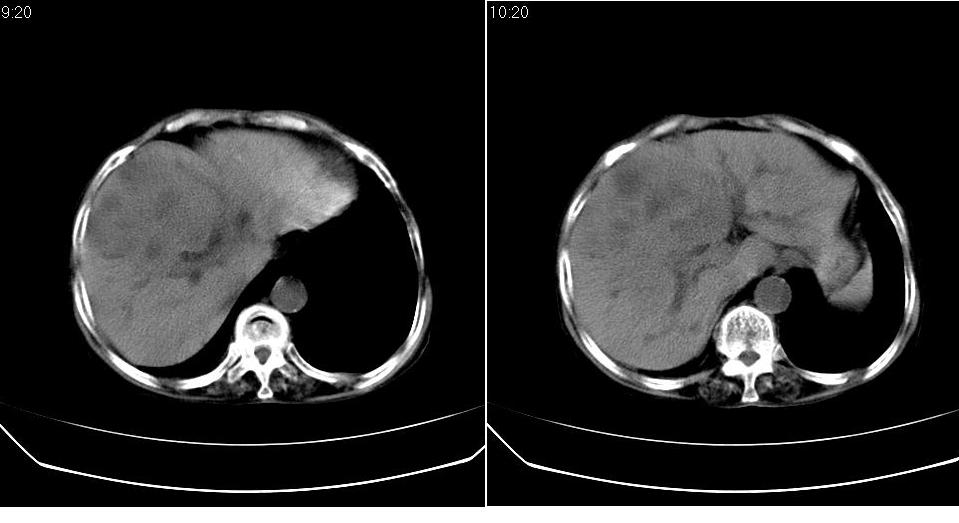

标题: CT23701:上腹部CT平扫

女 76岁,腹痛十余天。

肝癌、肝囊肿。

肝癌伴肝内胆管扩张,建议增强.

肝内胆管扩张,综合考虑胆管细胞肝ca!

考虑肝癌(胆管细胞型?)并肝内胆管扩张。